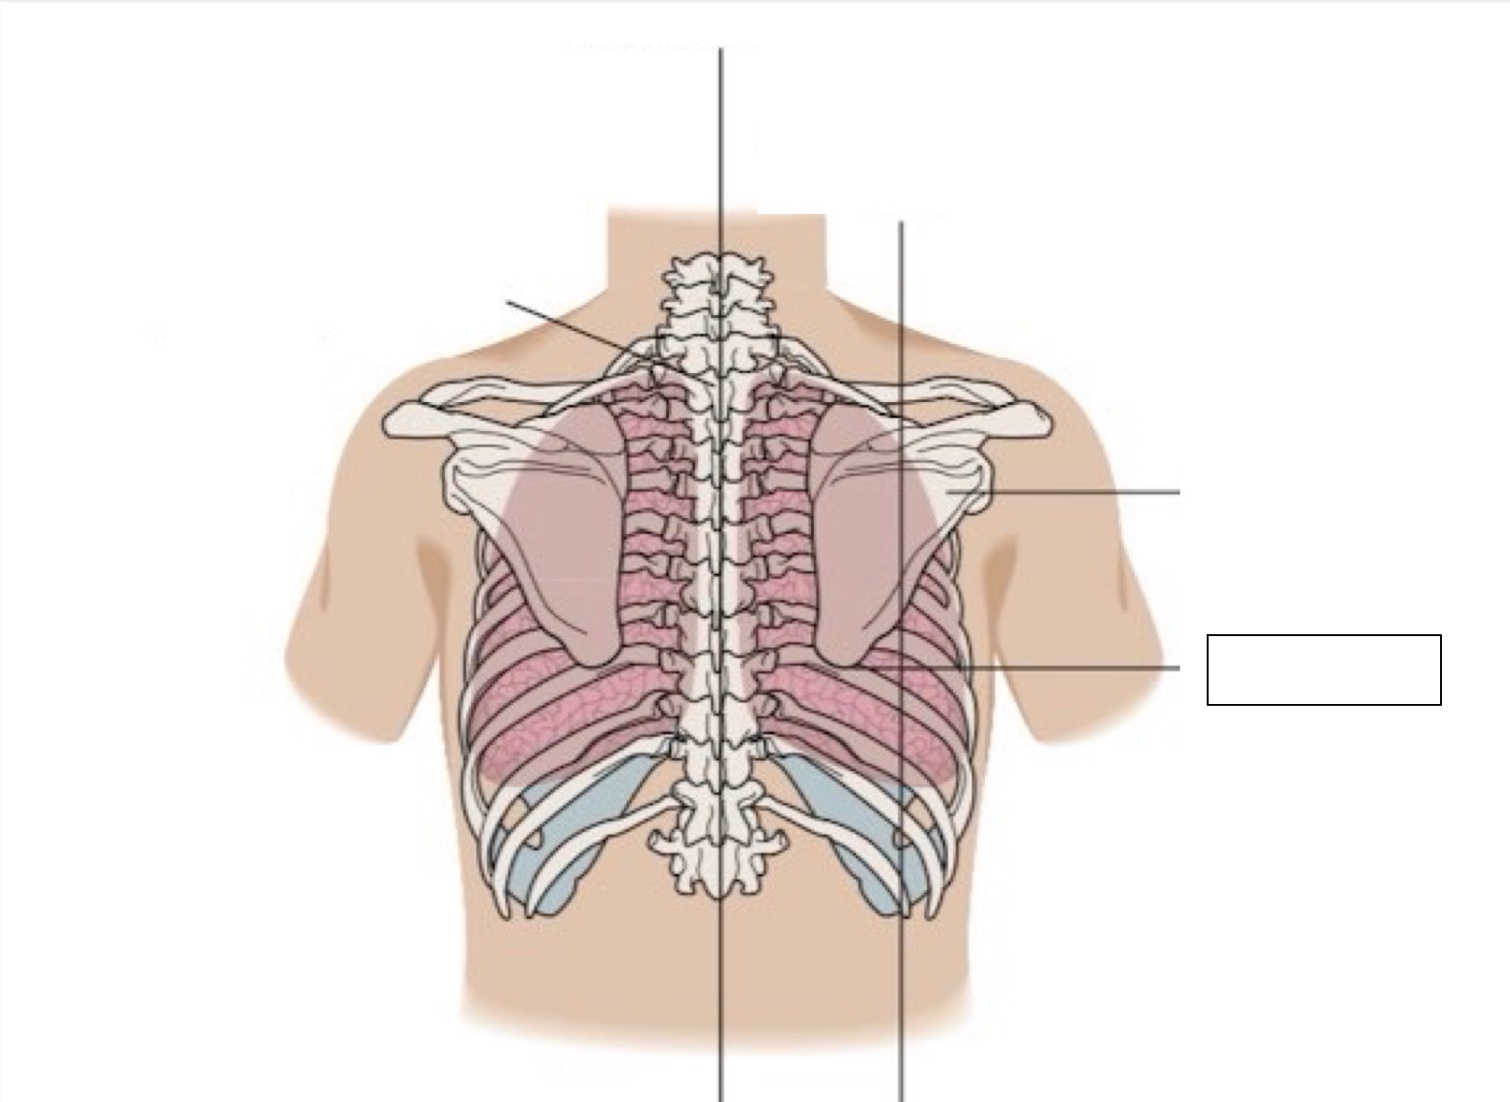

inferior angle of scapula

scapula

midscapular line

midspinal line

spinous process